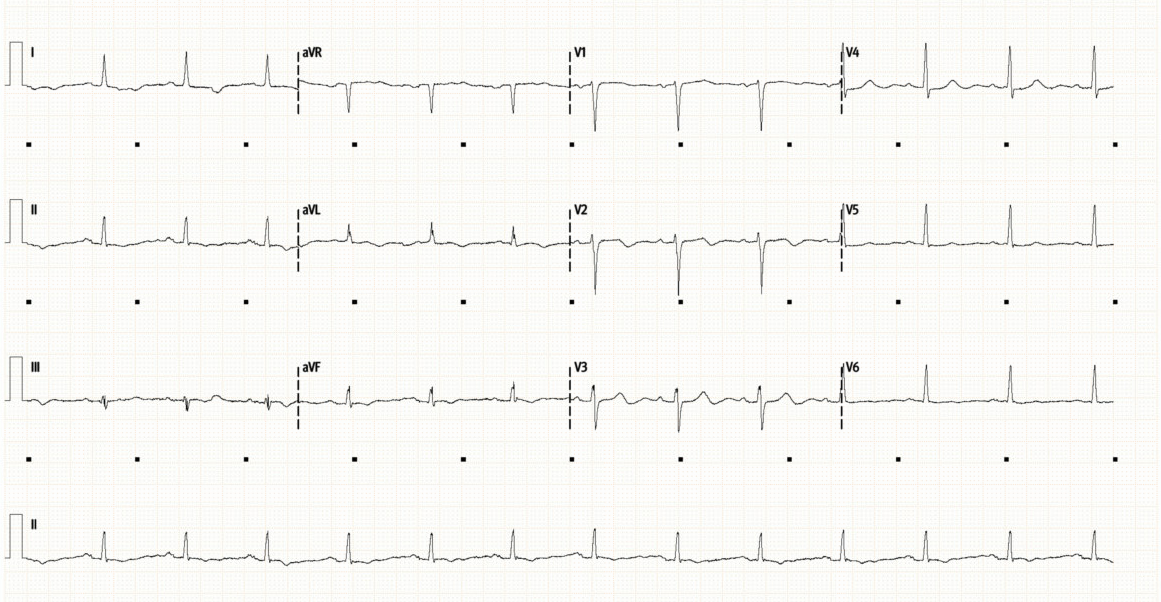

Below is her initial ECG (top), followed by repeat ECG 12 hours later (bottom).

Initial ECG (above), and repeat ECG (below)

• Initial ECG shows a sinus rhythm at 80/min with normal axis and intervals. There are no significant ST or T-wave abnormalities. This is a very unremarkable ECG.

• The repeat ECG shows some dynamic changes compared to prior. There is now subtle ST depression laterally (I, V4-6). There is new T-wave inversion in aVF, as well as new bi-phasic T-waves in V2/3. The T-waves laterally (V5/6) have also flattened compared to the initial ECG.

• Dynamic ECG changes are always concerning for myocardial ischaemia. There is no clear single territory involved here but acute MI needs to be excluded.

The patient had been having intermittent arm pain on initial assessment. At the time of the repeat ECG her pain had resolved. One differential for biphasic T-waves which appear when the patient is pain free is suggest Wellen’s syndrome, and are the result of coronary reperfusion, though typically seen in a vascular distribution (most commonly anteriorly in V2/3 signifying critical LAD stenosis). However, there are other conditions which can also cause non-specific T-wave changes.